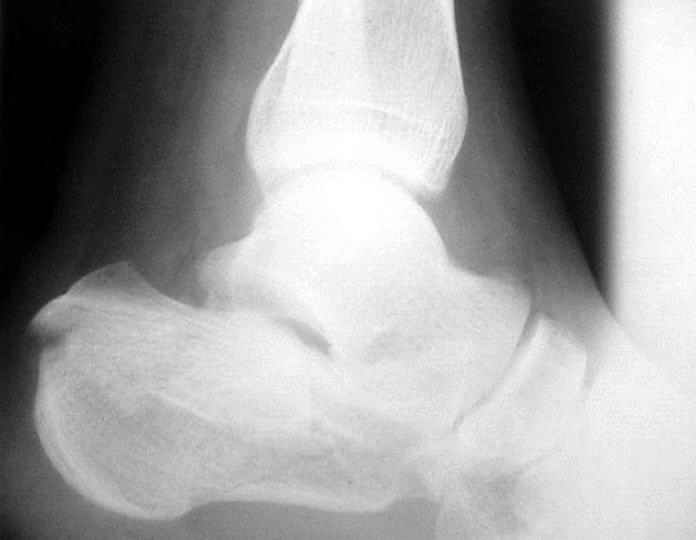

Пациент 36 лет поступил к нам с травмой стоп после падени яс высоты 6 м. С одной стороны подвывих в суставе Лисфранка, с другой переломпяточной кости (см. приложение).

Данный перелом можно классифицировать как "языкообразный" (по Essex-Lopresti), но имеется еще раздробление переднего отдела пяточной кости.

Судя по вашим рентгенограммам, восстановить суставную поверхность таранно-пяточного и пяточно-кубовидного сустава полностью не удалось, хотя угол Белера выглядит гораздо лучше, чем на предоперационной рентгенограмме,

что решает проблему посттравматического плоскостопия, восстановлена длина пяточной кости. Жаль, что возникла проблема с качеством томогафии. Интересно было бы знать, на сколько фрагментов была *расколота* суставная фасетка

В данном случае восстановлена лишь ось пятки - угол Белера в боковой проекции и смещение кнаружи и по длине в прямой. Гораздо проще и с несравнимо меньшим риском этого можно остигнуть, применив внешний остеосинтез.